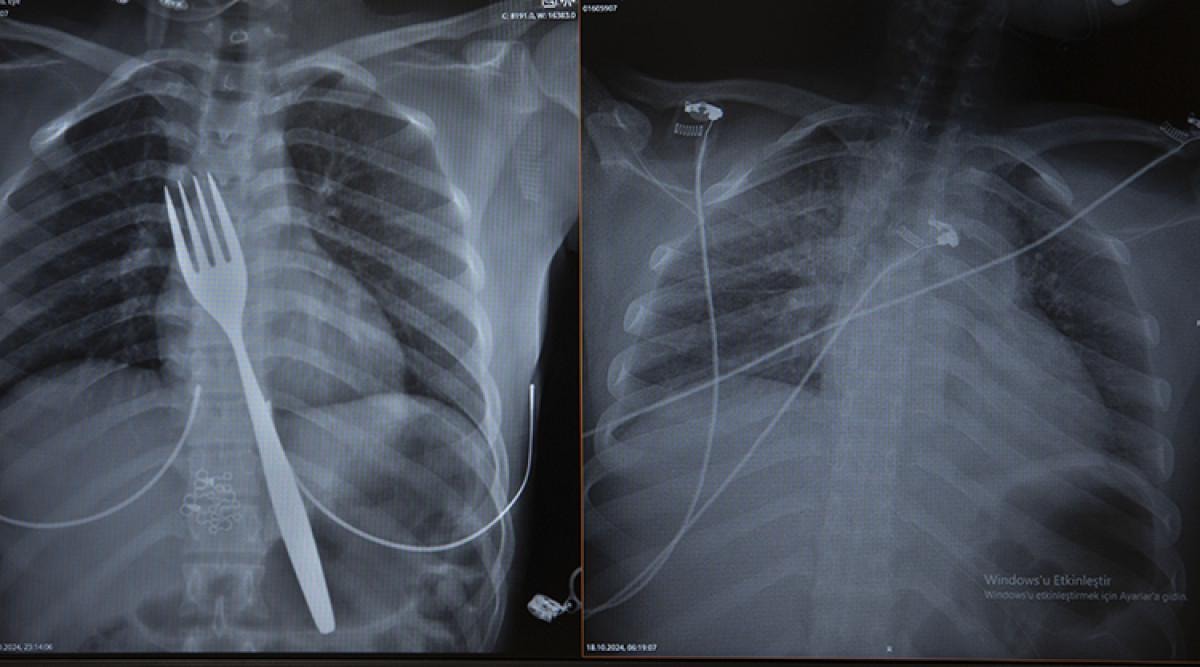

Burada röntgeni çekilen hastanın yemek borusunda 18 santimlik çatal olduğu tespit edildi.

Uzmanlar endoskopi yaparak çatalı ağızdan çıkarmayı denedi. Fakat yemek ve soluk borusuna zarar verme ihtimalinden dolayı midenin kesilerek çatalın çıkarılmasına karar verildi.

ADÜ Tıp Fakültesi Göğüs Cerrahisi Ana Bilim Dalı Öğretim Üyesi Dr. Salih Çokpınar ve Genel Cerrahi Ana Bilim Dalı Dr. Öğretim Üyesi Akay Edizsoy koordinasyonundaki operasyonla midede kesi açılarak çatal çıkarıldı.

Vakayı ilk duyduğunda şaşırdığını anlatan Edizsoy, "Büyük bir çatalın tamamen yutulması şeklinde ortaya çıkan bu vakayı ilk duyduğumda doğru olmadığını düşündüm. Hasta 18 yaşında ve yabancı uyrukluydu. Türkçesi biraz zayıf olduğu için belki de yanlış anlaşılmalar olabileceğini düşündük. Ama hastanın filmini çektiğimizde gerçekten bir çatalın yemek borusunda olduğunu gördük." dedi.

Biz en çok bu yüzden tedirgin olduk. Ama ciddi bir yaralanma olmadığını da yapılan endoskopiyle gördük. Endoskopi ile çıkarılamadı çünkü oldukça büyüktü ve endoskopik aletler için uygun değildi. Bu büyük bir yemek çatalı olduğu için kendi ağırlığı da var. Bir çivi gibi, iğne gibi tutulup çekilemiyor. Bundan dolayı karında yapılan kesi ile mideye ulaşıp midenin içinden bunu çıkarmak şeklinde bir strateji izledik. Yaptığımız bu ameliyatla da bu çatalı oradan çıkarabildik.